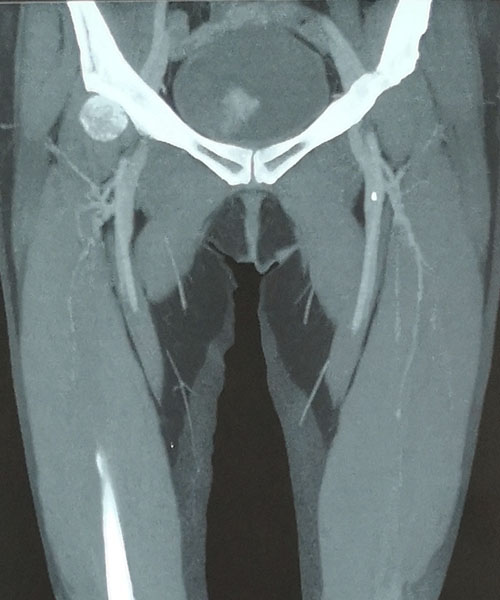

术前CTV评估股静脉及分支